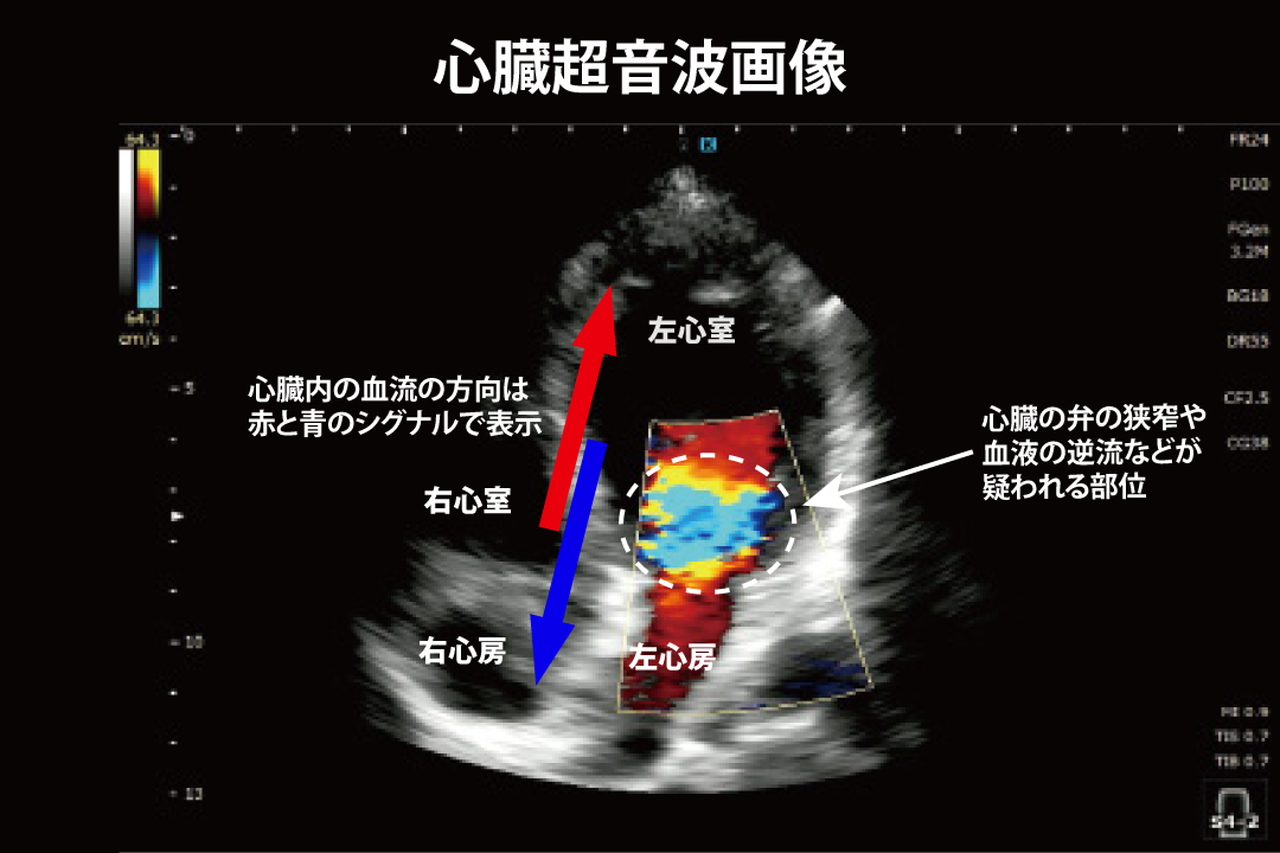

超音波検査機器は、身体表面から目標臓器に向けて超音波を放射し、その反射を測定することにより、形態を描出する機器のことを指します。全身の臓器の形態と動きを、リアルタイムに観察することが可能です。心臓に対して使用する場合には、心筋や弁の動きに加え、血流の向きや量まで評価することができます。当院では、特に心臓の超音波検査を頻回に実施しているため、その画質に定評のある米国GE(ジェネラル・エレクトリック)製の最上位機種を採用しております。循環器内科専門医として豊富なキャリアを持つ当院院長が、大学病院と同等の精度の検査を行っています。